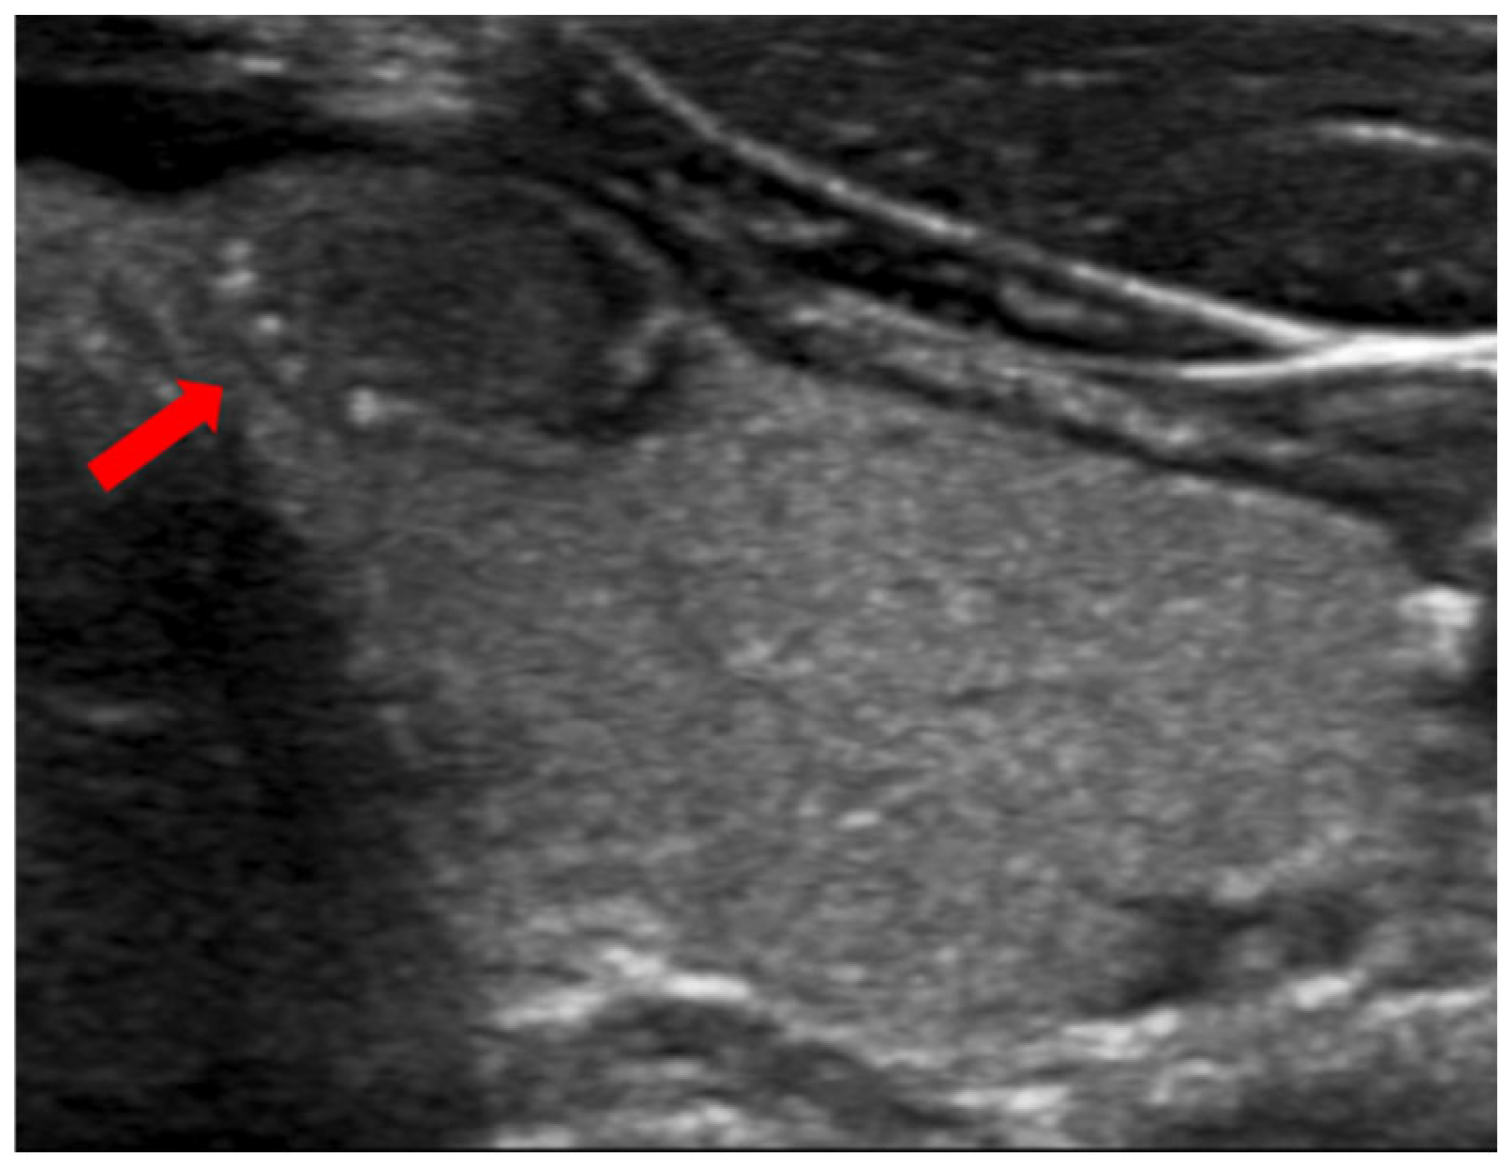

When a thyroid nodule has an anteroposterior (AP) dimension that exceeds its transverse (TR) dimension such that the ratio is greater than 1, it is classified as having a taller-than-wide shape (Figure 3). This observation was first reported in 2002 by Kim et al. in a study involving 155 thyroid nodules with an average size of 7.5 mm, of which 49 were malignant. This study found that a taller-than-wide shape was associated with a 92.5% specificity and 32.7% sensitivity for malignancy [51]. The authors proposed that this taller-than-wide configuration may reflect an underlying tendency for malignant nodules to grow across tissue planes, unlike benign nodules, that grow along tissue planes [51]. A meta-analysis and a systematic review by Brito et al., examining 31 studies and 18,288 nodules with an average size of 1.5 cm, reported that a taller-than-wide shape was associated with an OR of 11.1 (95% CI, 6.6 to 18.9) for malignancy [52]. In our study, we observed a significant association between a taller-than-wide shape and malignancy for nodules <1 cm but not for those above this size. For nodules <1 cm, a taller-than-wide shape was observed in 66.7% of malignant nodules compared to 5% of benign nodules (p = 0.03). In comparison, for nodules ≥1 cm, a taller-than-wide shape was seen in 14.6% of malignant nodules versus 13% of benign nodules (p = 0.67). Other studies have found similar findings [53,54]. In a study involving 207 nodules, of which 110 were malignant, Ren et al. found that a taller-than-wide shape was a good predictor for papillary cancer for nodules ≤1 cm but not for larger nodules [53]. In a study involving 1238 nodules, of which 159 were papillary cancers, Kim et al. found that a taller-than-wide shape was associated with an OR for cancer of 2.7 (95% CI, 1.7 to 4.3) (p < 0.001) for nodules ≤1 cm vs. an OR of 1.2 (95% CI, 0.4 to 3.2) (p = 0.77) for nodules >1 cm [54].

Figure 3. A benign nodule with a taller-than-wide shape.